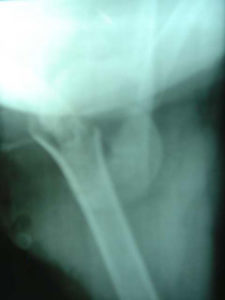

Fractures around Shoulder Before Surgery

Before Surgery